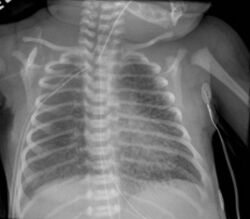

Emphysema low mag.jpg

Micrograph of an emphysematous lung; emphysema is a rare respiratory disease, strongly associated with smoking. H&E stain.